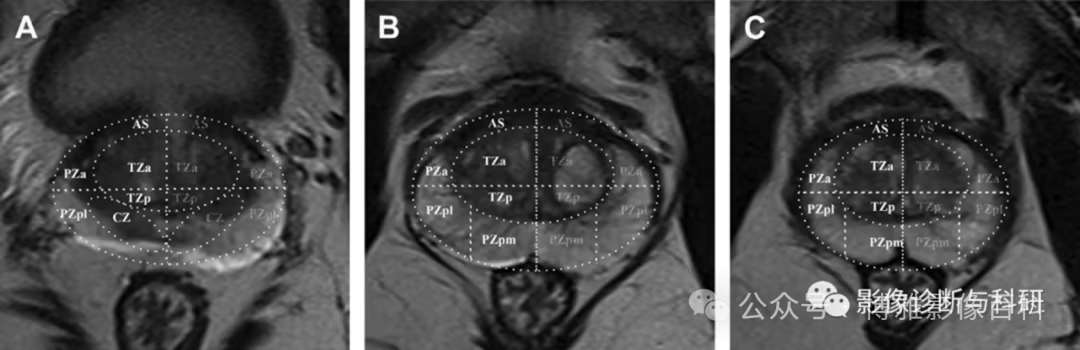

扇区解剖

PI-RADS 第 2 版中使用的扇区图使用了 39 个扇区(14 个在基底部,12 个在中部,12 个在前列腺尖部,2 个精囊和 1 个尿道括约肌)。在 2.1 版中,为基底部的左右后内侧 PZ (PZpm) 增强加了两个额外的扇区(见下图,红色)